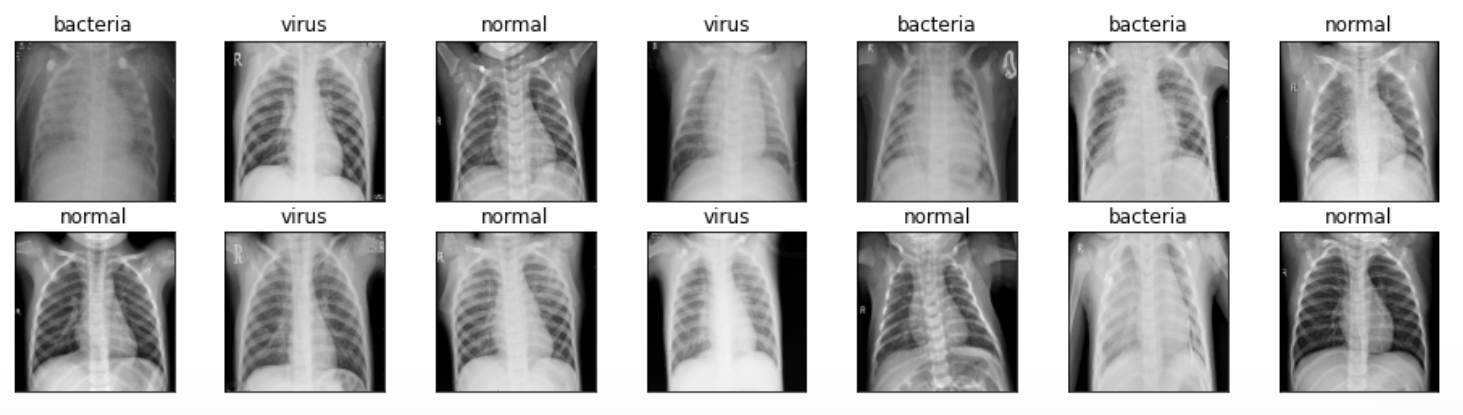

可以说,在这个阶段,并非强制要求必须显示几张图像。然而我想通过这一操作来确认图片是否已经被正确加载并进行了必要的预处理工作。下面的代码段将用于展示从X_train数组中随机选取的14张图片及其对应的标签信息。

fig, axes = plt.subplots(ncols=7, nrows=2, figsize=(16, 4))

通过观察上图中的每一幅图像可以看出,在当前版本中所有图像的尺寸均一致,并与我在本帖子中所使用的封面图片有所区别